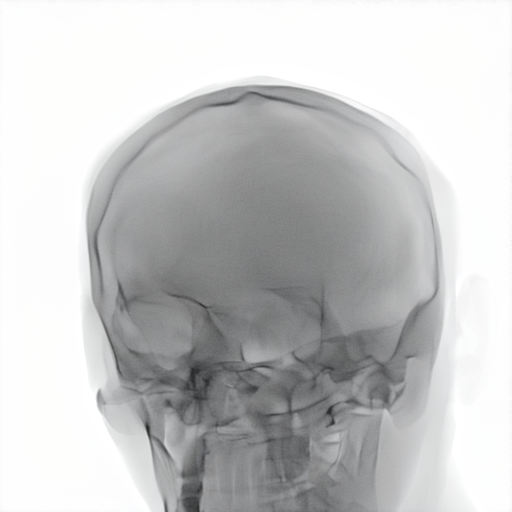

Refer to caption

Figure 2: Dataset overview. The synthetic domain contains Low and High dosage samples generated using the Mentice VIST® simulator; the real domain includes Low, Normal, and Exposure dosage categories acquired from a skull phantom using the Philips Azurion IGT system.

We develop and release a new dataset of real and synthetic head X-ray images, X-DigiSkull, to study the domain adaptation. The dataset consists of synthetic X-ray images of a human skull generated using the Mentice VIST® simulator 111https://www.mentice.com/simulator/vist-g7. Real‑time X‑rays are generated by holding the 3D voxel “patient” head model with per‑voxel attenuation, casting one ray per detector pixel to form a digitally reconstructed radiograph and then approximating scatter, focal‑spot and detector blur, grid/heel effects and detector response, adding quantum/read noise and final image post-processing as the C‑arm and devices move. Real images are acquired from a clinical-grade physical skull phantom using the Philips Azurion Image Guided Therapy (IGT) system. Images are captured from common IGT working positions for neuro procedures. The dataset consists of multiple orientations and is available in three different radiation dose settings: low, normal, and exposure (Philips exclusive), the latter offering enhanced image quality and detail, as shown in Figure 2. This consists of viewing angles rz[40,+40]r_{z}\in[-40^{\circ},+40^{\circ}], ry[40,+40]r_{y}\in[-40^{\circ},+40^{\circ}], rx[40,+40]r_{x}\in[-40^{\circ},+40^{\circ}] with respect to the starting position in 10 increments and up to 3 images at each position to capture the noise present. This results in a total of 2,187 real images. The coordinate systems of the real and synthetic environment are aligned and synthetic images are rendered to approximate the same viewpoints as the real phantom images with the patient table starting at a similar position.The head 3D model used in the simulation is meticulously built from a real clinical case. We capture the synthetic images in finer increments of 5 across the three angles, producing the 5,832 (18318^{3}) images 222Data available at https://zenodo.org/records/16535437. The aim of this alignment is not to achieve precise supervised image translation, but rather to establish a consistent reference structure that preserves spatial features. The composition of the dataset is summarized in Table 1, which contains information on the splits and the number of images available. All images are cropped and resized to 780×\times780 pixels. The test set is obtained by uniformly sampling 15% of viewing angles and corresponding images to ensure a representative distribution. For our experiments, we focus on the task of converting synthetic images at high dose to real images at normal dose.